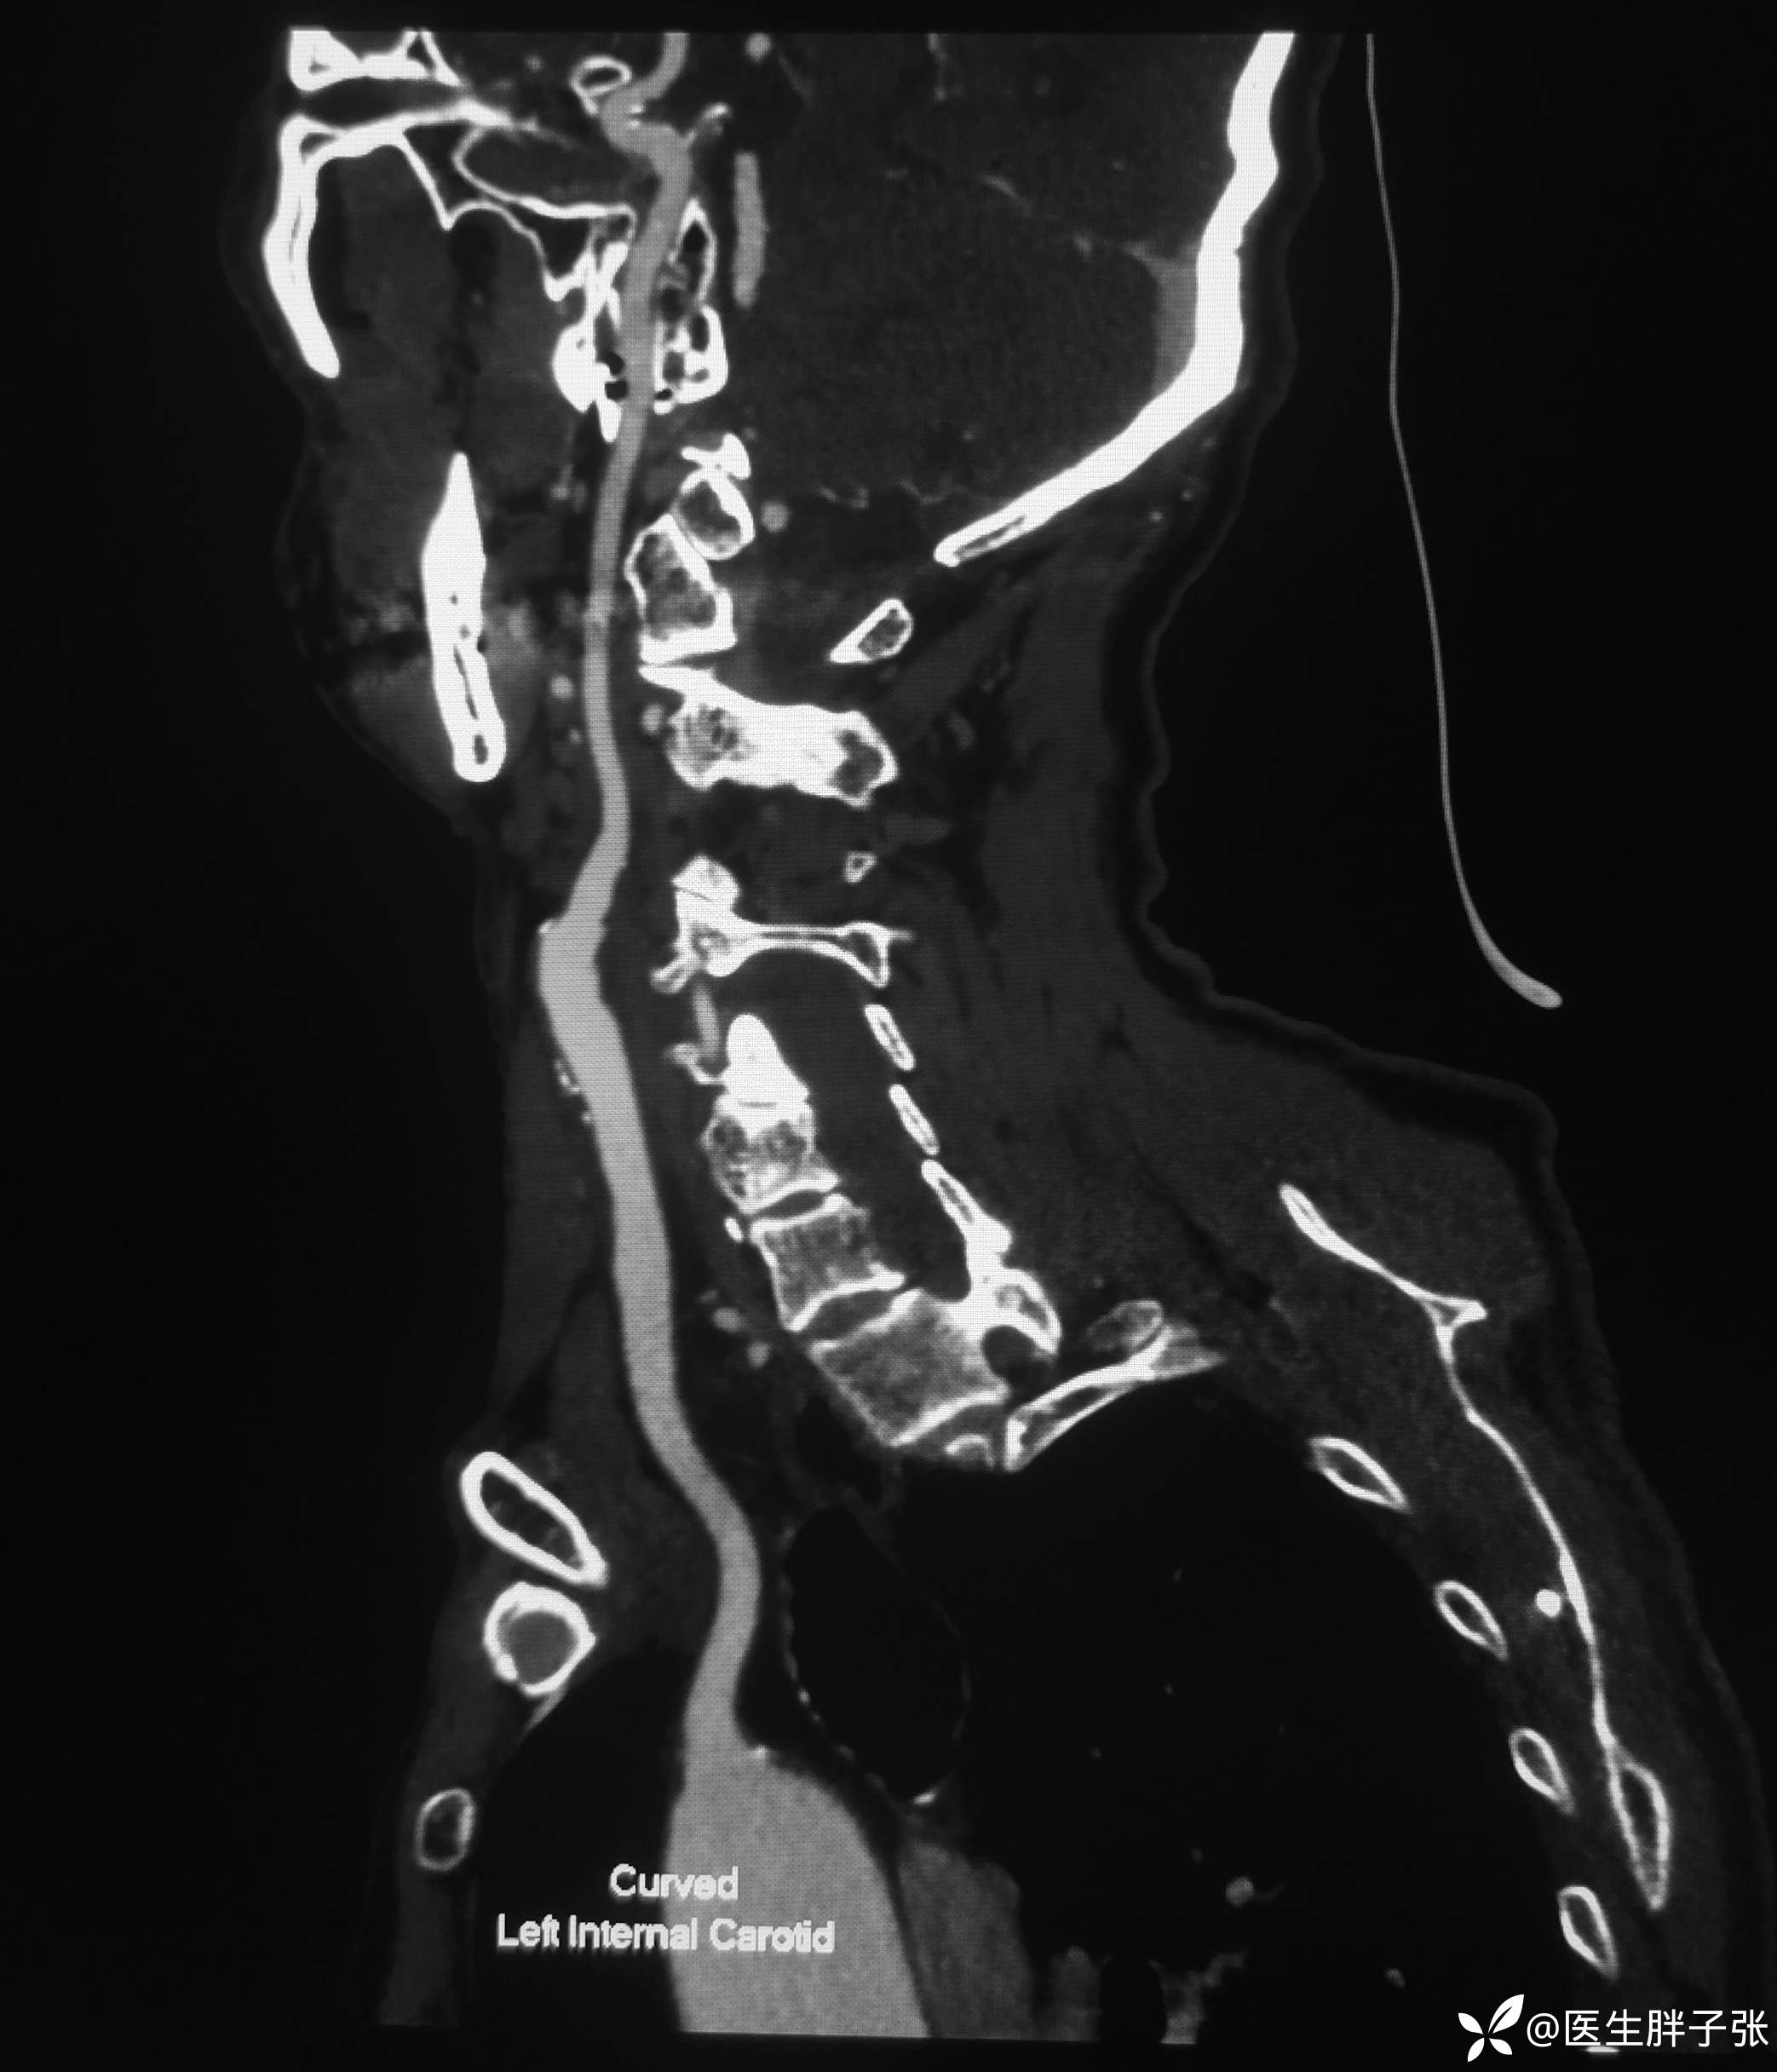

头颈部CTA